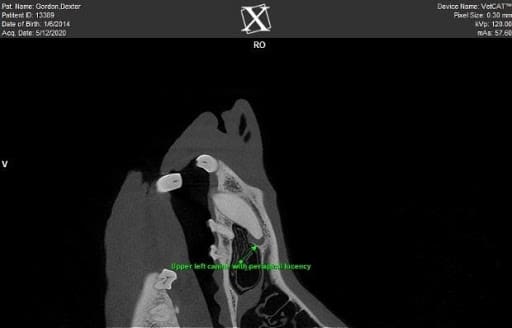

Figure 2 – A cone beam computed tomography image of an abscessed left upper canine tooth.